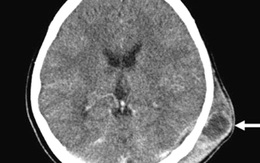

'Bệnh lạ' của mẹ bé gái hiếu thảo ở Bình Định, làm sao tránh?

Bệnh lạ chính là bệnh áp xe dưới da đầu. Ngoài ra bệnh nhân còn bị các bệnh người cao tuổi hay gặp như tăng huyết áp, rối loạn tuần hoàn não.